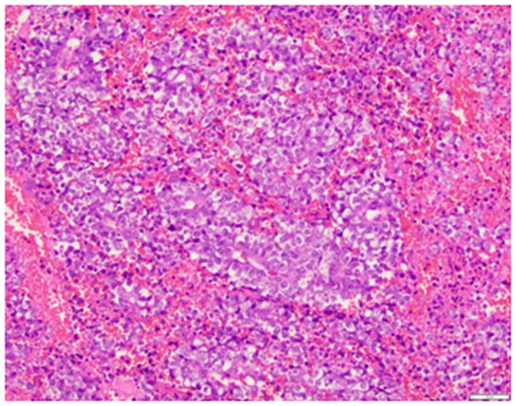

A 52 year old G1P1001 female with a history of hypertension, hyperlipidema, depression, and schizoaffective disorder presented with the primary complaint of a painful left sided vaginal mass. She also complained of irregular heavy menses for the past three months. On pelvic exam, the vaginal mass was diagnosed as a left Bartholin gland abscess that measured 2x3cm and was noted to be indurated. The remainder of the pelvic exam was unremarkable. The patient was offered incision and drainage for which she declined. She was started on Augmentin. Perimenopause was thought to be a contributing factor of the patient’s irregular menstrual pattern. As part of screening guidelines, Papanicolaou smear was performed and was found to be remarkable for atypical glandular cells of undetermined significance. Endometrial biopsy (EMB) was recommended. The patient was lost to follow up for two months. She eventually returned to clinic and reported improvement in the abscess after antibiotics, but recurrence after discontinuation. During her follow up visit, EMB and incision & drainage of the Bartholin abscess with placement of Word catheter was performed. However, due to the exuberant amount of indurated tissue expressed from the Bartholin abscess, a tissue specimen of the Bartholin abscess were sent to pathology for evaluation. The pathology report returned a poorly differentiated malignant neoplasm favoring carcinoma for the Bartholin gland sample as well as the endometrial biopsy sample. The tumor was described as poorly differentiated and consisting of enlarged nuclei with vesicular chromatin, perinuclear clearing, occasional prominent nucleoli, moderate amounts of amphophilic delicate cytoplasm, and increased mitoses (Figures 1 & 2). There was also extensive tumor necrosis seen in the specimens (Figure 3). The patient underwent CT of her chest, abdomen, and pelvis, as well as a PET CT of the skull to thigh. Her CT revealed a 10.8 cm poorly defined endometrial and myometrial neoplasm, with metastatic disease to the right iliac node, right parametrial nodes, periaortic lymph nodes, and bilateral adrenal glands. There were no other significant findings on CT. Her PET scan showed prominent Fluorodeoxyglucose (FDG) activity in the uterine mass and left adrenal mass, with a smaller amount of FDG activity in a large right pelvic lymph node adjacent to the uterine mass, with no other contributory findings (Figure 4). She was referred to the care of medical oncology, and during the patient’s Gynecology Tumor Board case presentation the pathologists concluded that her poorly differentiated cancer was uterine in origin. Due to the extent of metastatic disease she was recommended medical management. She was started on a Paclitaxel and Carboplatin chemotherapy therapy.

Figure 1 Medium power view of the poorly differentiated tumor, consisting of enlarged nuclei with vesicular chromatin, peri–nuclear clearing and occasional prominent nucleoli (H&E, 20x).